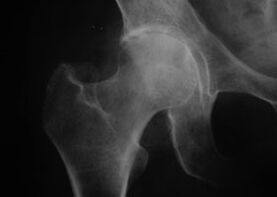

Coxarthrosis, arthropathy of the hip joint

With this disease, a classic clinical picture of arthritis is observed.

The first symptom of coxarthrosis is discomfort in the hip joint after physical activity.

With progressive coxarthrosis, pain increases, stiffness and limited mobility appear.

Patients with a severe form of coxarthrosis take care of the affected limb, avoiding stepping on it and while they are still, they choose positions in which the pain is less noticeable.